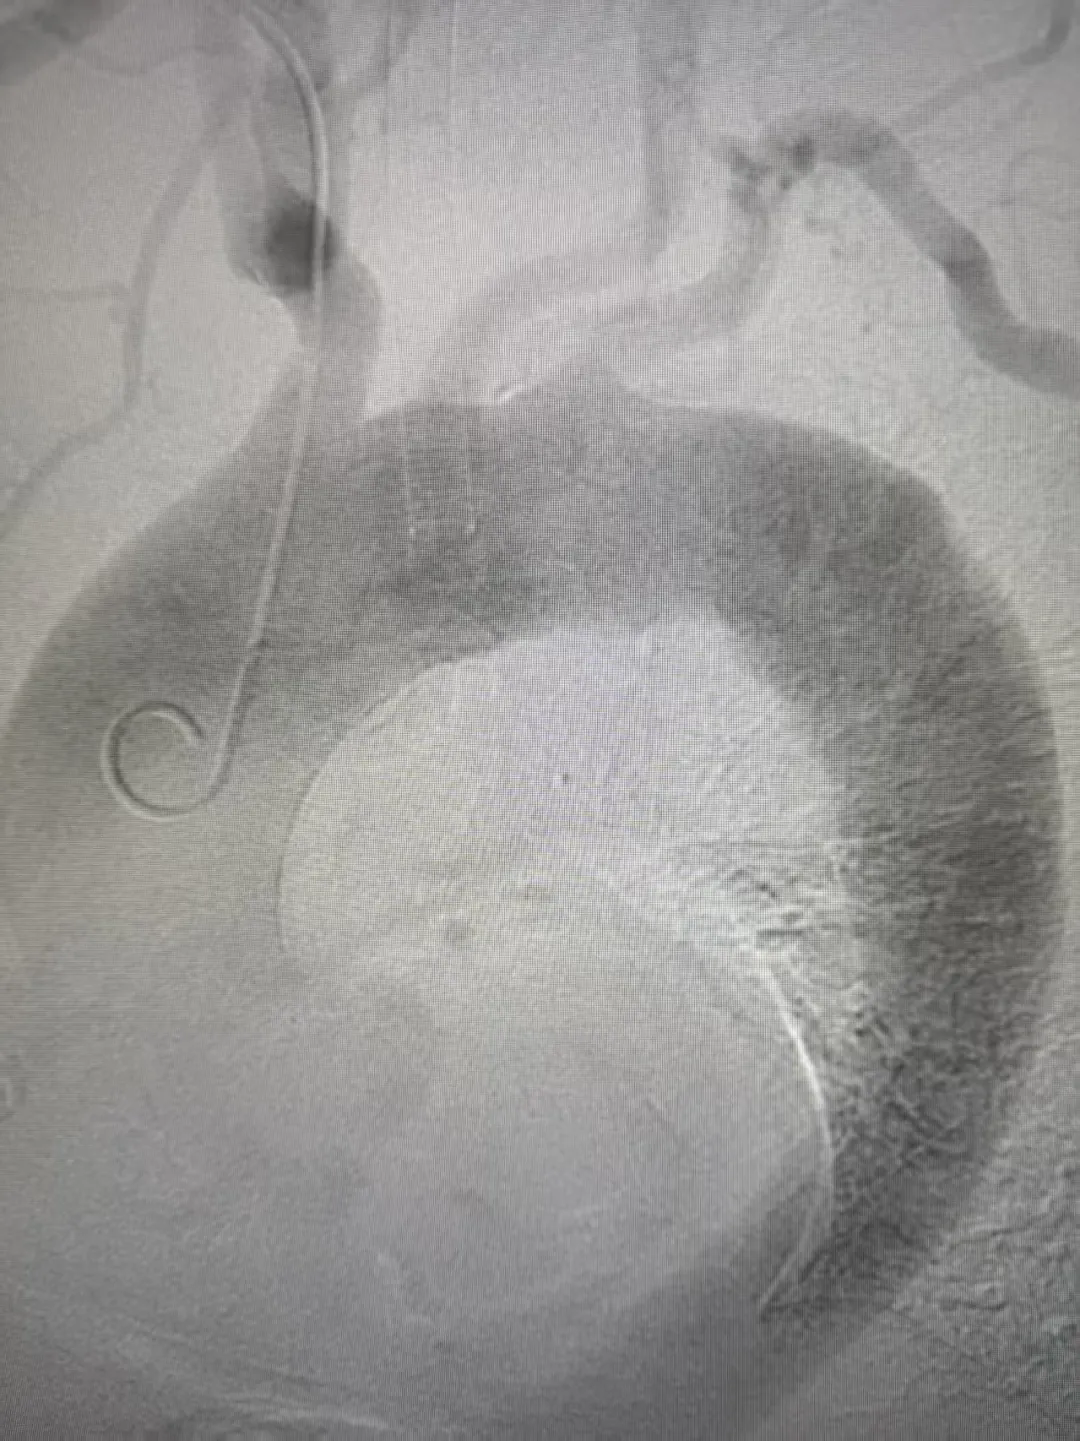

71岁的彭大爷因突发胸痛紧急入院,完善检查后确诊为胸主动脉壁间血肿—— 这是临床极为凶险的主动脉急症,发病急、进展快,血管随时可能破裂,致死率极高,精准、快速的诊疗方案成为挽救患者生命的关键。

(术前造影) 面对患者的危重病情,外四区第一时间启动多学科诊疗机制,组织科内专家开展病例研讨,并特邀汕头市中心医院教授远程会诊,专家团队一致确定为患者实施胸主动脉腔内修复术,并决定启用揭阳地区首台Cratos分支型覆膜支架及输送系统。手术过程顺利,术后患者胸痛症状即刻缓解,生命体征平稳,在医护团队的精心护理下,恢复状况良好,现已无胸闷胸痛等不适,顺利康复出院。